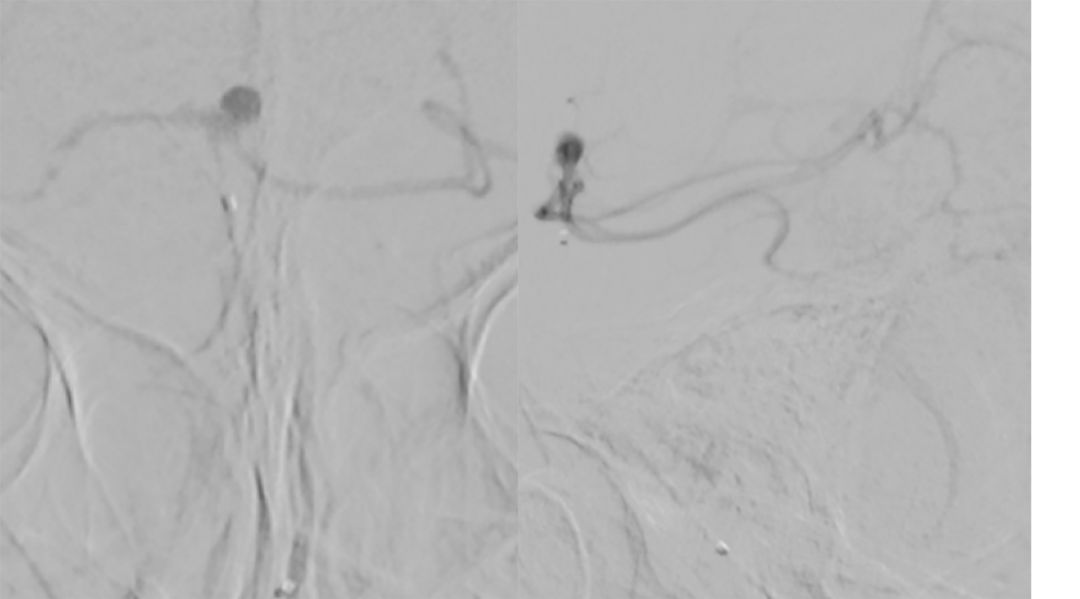

全脑血管造影(本院,2019-8-1 ):基底动脉顶端夹层或者开窗,左侧小脑上动脉瘤(图4)。

图4

2. 将Echelon-10微导管置入基底动脉较粗的管腔中进行微量造影(正位、侧位)(图6):左侧大脑后动脉显影。

图6

3. 再将Echelon-10微导管置入基底动脉较细的管腔进行微量造影(正位、侧位)(图7):双侧大脑后动脉及左侧小脑上动脉显影,可见动脉瘤位于左侧小脑上动脉。

图7

4. 最后将Echelon-10微导管置入基底动脉中下段进行微量造影:基底动脉2个管腔、 双侧大脑后动脉显影、小脑上动脉均可显影(图8)。

图8

基底动脉进行三维血管重建:基底动脉有较粗和较细的2个管腔,左侧小脑上动脉瘤大小约2.3*2.1 mm(图9)。

图9

进行上述三次微量造影均可见双侧大脑后动脉显影,以及结合基底动脉三维重建图像,故判断基底动脉属于开窗,而非夹层。由于载瘤动脉较细,拟行单微管动脉瘤栓塞术。